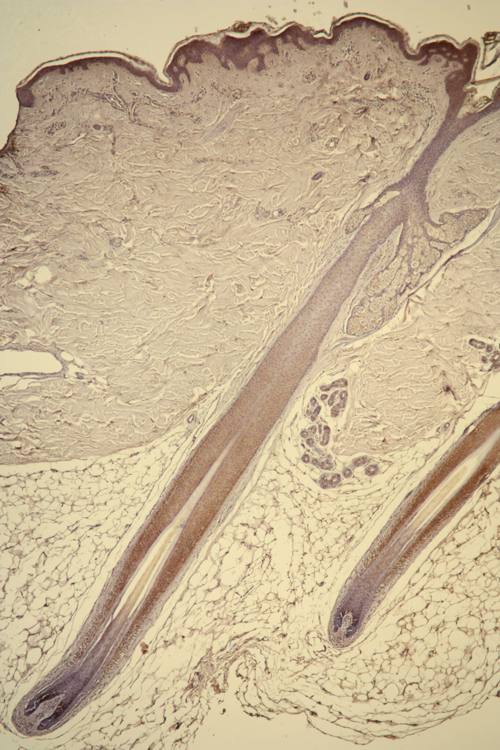

LB: In androgenic alopecia, the androgen hormone kills off one of the cell populations in the hair follicle that’s responsible for hair growth. They’re called the dermal sheath cup cells and sit at the base of the hair follicle. The androgen hormone attaches to a cell receptor on the surface of those cells. That same cell population located at the back of the head simply lacks the receptor for the androgen hormones to use in its attachment. So, those cells are essentially mechanically immune to the condition and that’s why people with pattern baldness usually have hair on the back of their head.

hair-follicle-21497365732173.png

As a result, we start with a tissue biopsy at the back of the head and isolate those cells which are immune to the condition and grow millions of more cells to repopulate the follicles on top of the head.